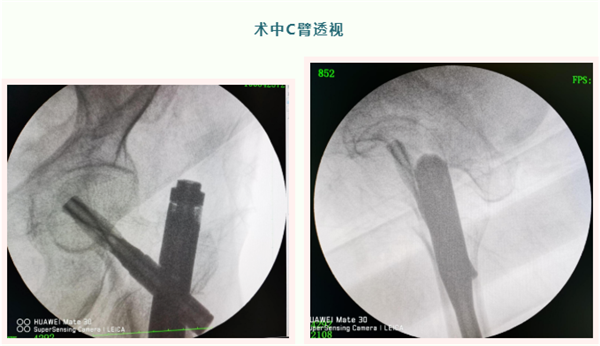

我院常规采用闭合复位PFNA内固定术,手术创伤小,结合中医辨证施治,调理气血。术后恢复快,大多数患者都能走着出院,大大减轻了患者的痛苦,减少了家庭及社会负担。

骨伤科一位老奶奶今年84岁,在家看鸭子时不慎摔伤,致左髋部骨折。